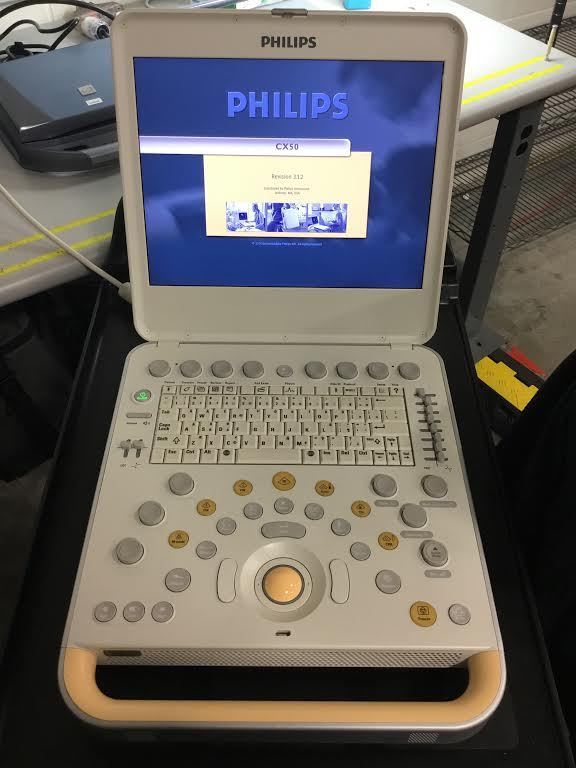

DIAGNOSTIC ULTRASOUND MACHINES FOR SALE